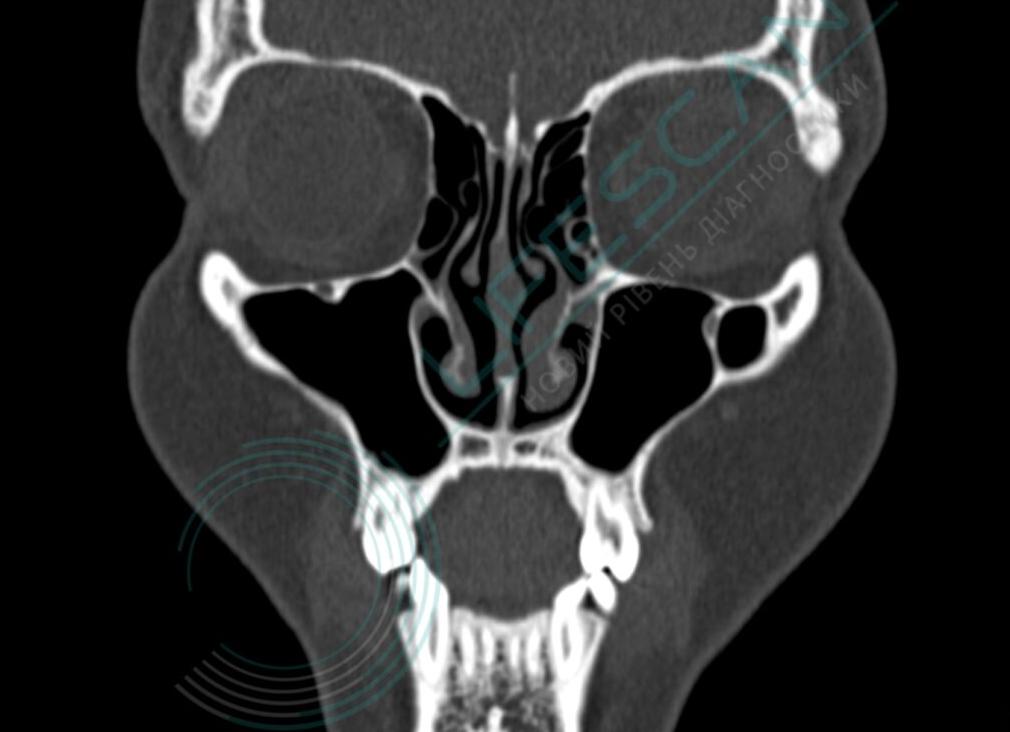

С помощью компьютерной томографии околоносовых пазух врач может рассмотреть в подробностях строение и текущее состояние носовой полости и четырех придаточных пазух носа (далее ППН):

- лобных — расположенных в лобной кости и имеющих вид треугольников;

- гайморовых — расположенных справа и слева от носовой полости в верхнечелюстной кости;

- клиновидных — расположенных внутри клиновидных костей черепа;

- решетчатого лабиринта — расположенного в месте соединения носовой кости с черепом (в области переносицы).

На КТ-снимках придаточных пазух носа четко видны любые изменения, включая воспалительные процессы, скопления экссудата, гноя, крови или жидкости, нарушение целостности костей, хрящей и мягких тканей (в том числе слизистой оболочки, кровеносных сосудов и нервов).

Постановка диагноза осуществляется по таким параметрам исследуемых тканей, как их структура, плотность, степень минерализации тканей и их объем.